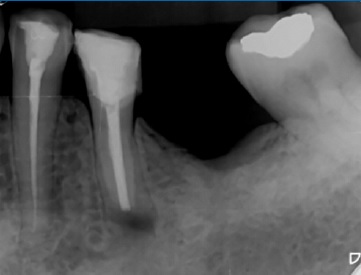

Ao exame radiográfico (Figura 2) foi possível identificar uma área radiolúcida unilocular, de contorno mal definido, na região periapical do dente 35, estendendo-se para o periápice do dente 34 e região edêntula correspondente ao 36. Para melhor visualização da extensão da lesão e sua relação com o canal mandibular foi realizada Tomografia Computadorizada de Feixes Cônicos. Cortes axiais e parassagitais mostraram rutura das corticais ósseas vestibular e lingual do corpo da mandíbula, além do íntimo contato da lesão com o canal mandibular (Figura 3), revelando o elevado risco de parestesia do nervo alveolar inferior e do seu ramo mentoniano, após intervenção cirúrgica.

Figura 3 Cortes de tomografia computadorizada mostrando imagem hipodensa (IOH), na região periapical do dente 35 (D35) e região do dente 36 (R36) causando rompimento da face lingual da cortical do canal mandibular (CM) e das corticais ósseas vestibular e lingual da mandíbula, além de proximidade com o forame mentoniano (FM).